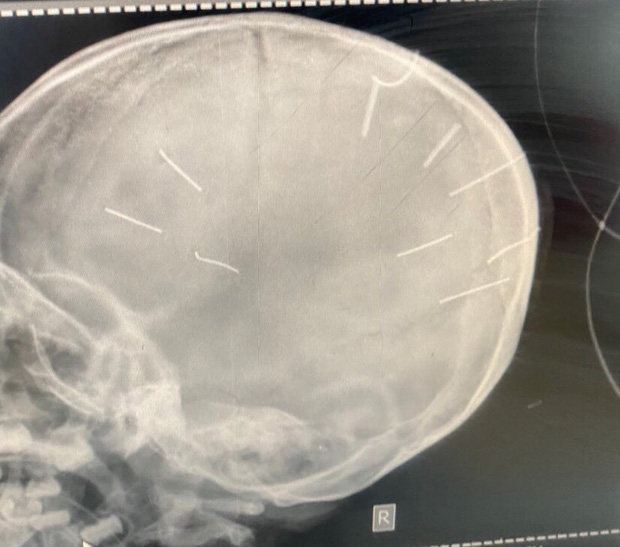

9 chiếc đinh trong đầu bé A được BV phát hiện qua chụp X-Quang

Trao đổi với PV về vấn đề này, PGS.TS Nguyễn Tiến Dũng (nguyên trưởng khoa Nhi, bệnh viện Bạch Mai), cho biết cấu tạo hộp sọ của các cháu nhỏ hiện đang phát triển, có những đường thóp còn mềm, nếu sờ vào đúng những khe đấy thì rất dễ cho đinh vào sâu.

PGS.TS. Nguyễn Tiến Dũng phân tích với trẻ khoảng 3 tuổi thì đa số các đường thóp đã liền, tuy nhiên cũng có nhiều trẻ vẫn chưa liền, mà kể có liền rồi thì cũng chưa hoàn chỉnh. Tóm lại với trẻ nhỏ thì vỏ hộp sọ còn mềm, còn phát triển rộng ra và còn có thể có những đường khớp rạch giữa, rạch ngang xung quanh. Nên nếu vô tình đóng đinh vào vùng đó thì trẻ ít đau.

Ngoài ra, theo PGS Dũng, không chỉ riêng trẻ em mà kể cả người trưởng thành, ở trên não có những vùng câm, là những vùng não mà không có biểu hiện ra bên ngoài, chọc vào không gây liệt mà cũng không chết, thậm chí là cũng không chảy máu, dị vật cứ xuyên vào sâu và ở trong như vậy. Nhất là đinh ghim nhỏ diện tích tiếp xúc nhỏ, không cần lực mạnh thì khó để lại dấu vết. Còn nếu chọc đúng những đường đi có dây thần kinh thì liệt ngay lập tức, hoặc chọc đúng vào chỗ liên quan đến hô hấp tuần hoàn thì đứa trẻ có thể chết ngay.